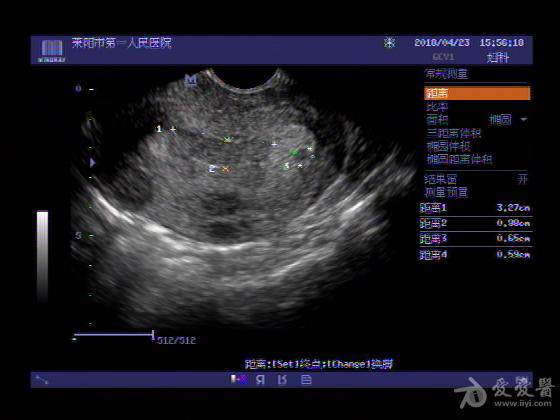

女,48岁,月经量多,两个月,一年前出现过类似现象,刮宫吃药后缓解。

超声可见:子宫内膜显著增厚,后肌壁内膜可见范围约3.27X0.90CM低回声区,CDFI显示较丰富线样血流,宫底宫腔内见类**状低回声结节。前肌壁见多发类圆形低回声结节。

超声提示:子宫内膜增厚(建议刮宫病理),子宫多发肌瘤

病理结果:内膜增生